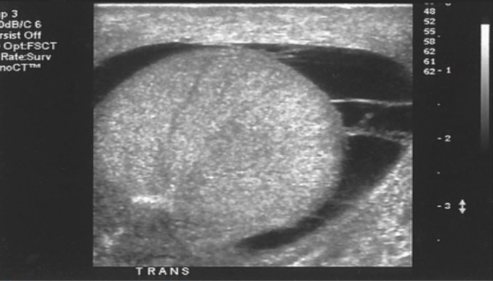

Identify the echogenicity

Anechoic